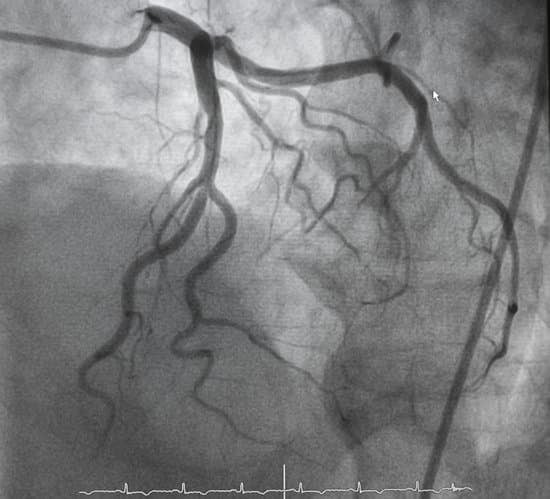

혈관조영술(Angiography)에 대한 이해

혈관조영술은 혈관의 상태를 검사하는 의료 영상 진단 방법입니다.

이 검사는 혈관 내부를 시각화하여 혈류의 이상, 혈관의 좁아짐, 막힘, 기타 혈관 문제를 평가합니다.

심장 질환 평가

관상동맥 질환, 심장마비, 협심증 등 심장과 관련된 혈관 질환의 진단에 사용됩니다.

영상 촬영: X-레이, CT, MRI 등을 사용하여 혈관의 이미지를 촬영합니다. 이를 통해 혈관의 형태와 혈류 상태를 평가합니다.